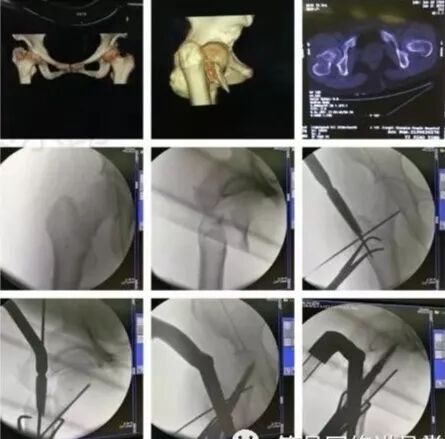

2)骨盆骨折

30min,三个决定:

• 开放性骨折,立即止血;

• 骨盆制动(10-15min);

• 观察10-15min,血流动力不稳定,能否手术?

图片

血流动力学稳定,在7天内手术?